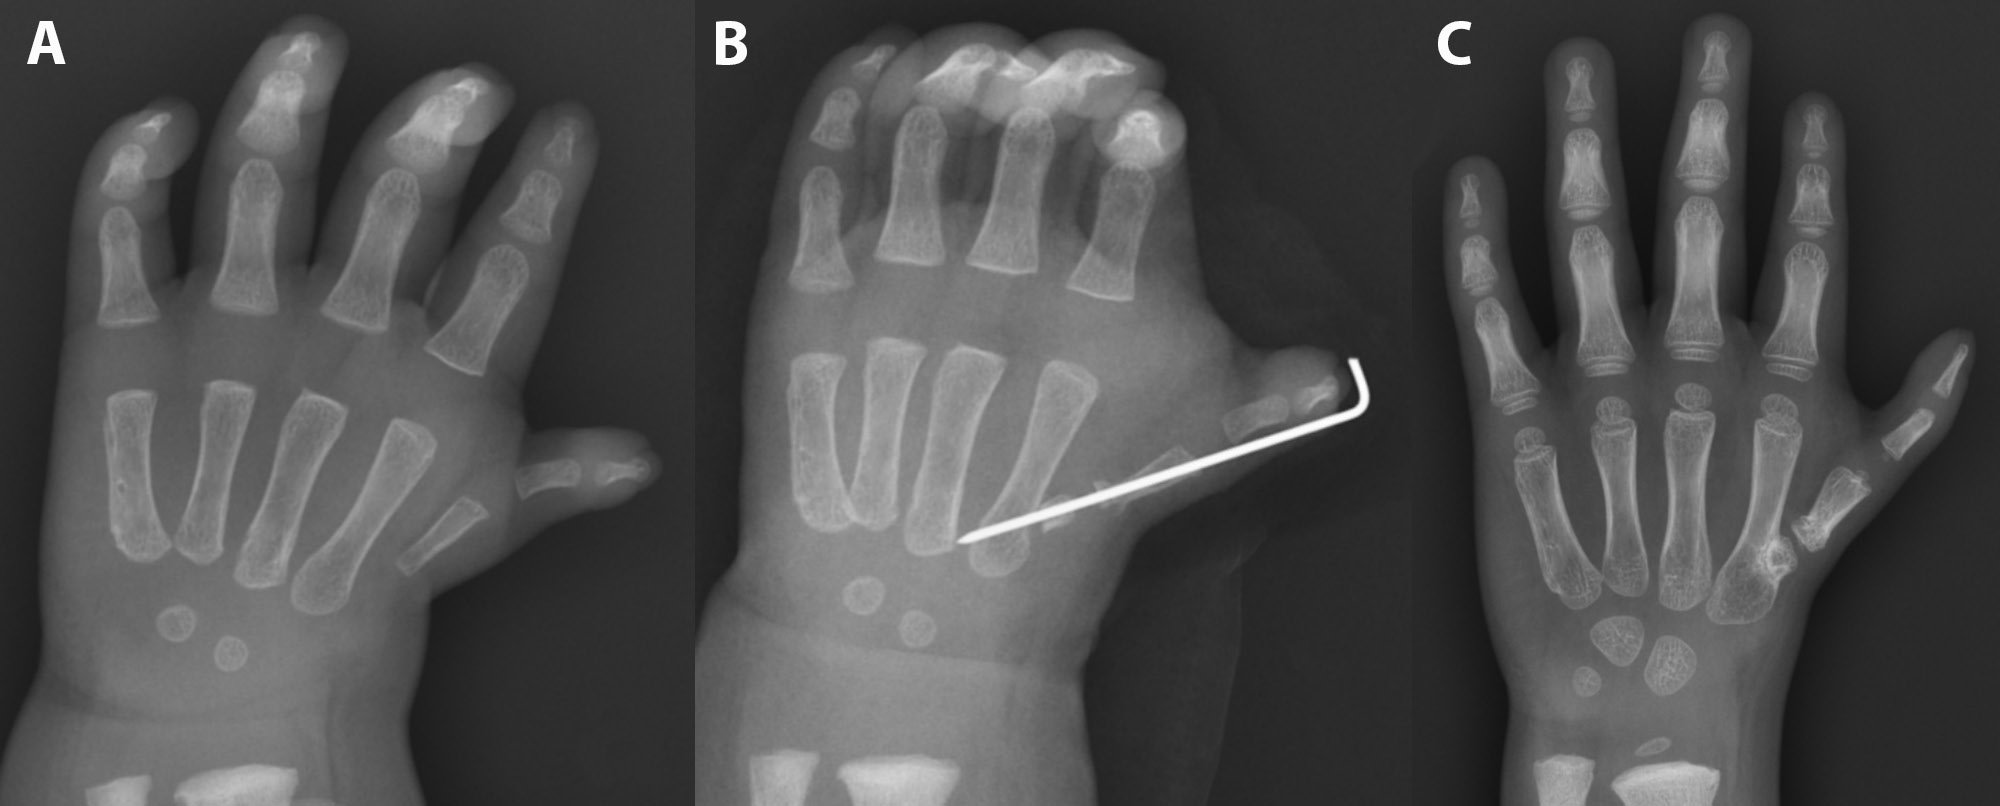

Between 2000 and 2022, our hand surgery department treated 25 patients with type III B thumb hypoplasia whose parents declined gold-standard pollicization – due to the resulting 4-fingered hand – and instead opted for alternative reconstructive techniques. For this reason, we proposed and performed an alternative reconstructive surgery by stabilizing the hypoplastic thumb using a non-vascularized PIP joint from the foot. An additional inclusion criterion required that the affected thumb have no history of prior surgical intervention. The surgical technique and related procedural details have been described comprehensively in an earlier publication (Figure 1).24

Eight patients participated in the study, including 4 girls (50%) and 4 boys (50%), aged 3–15 years, with an average age of 8 years and 6 months. The defect was unilateral in 7 cases and an isolated thumb defect in 5 cases. Three cases involved a complex upper extremity defect, such as congenital radial deficiency. One patient had additional diagnoses of congenital hearing loss, hydrocephalus, and thumb aplasia in the contralateral hand. The children underwent between 1 and 4 surgeries (median: 1.5), with thumb stabilization using PIP joint graft often being the 1st procedure performed. Additional procedures included wrist centralization and ulnar bone lengthening. The age at the time of surgery ranged from 1 year to 3.5 years, with the median age of 1 year. Five right hands and 3 left hands underwent surgical procedures. The donor PIP joint was harvested from the right foot 7 times and from the left foot once. In 75% (6/8) of the cases, the grafts were obtained from the same side as the operated hand. The 3rd toe was most frequently used as the donor site, accounting for 63% of the cases, while the 4th and 2nd toes were used as the donor sites in 25% (2) and 12% (1) of the cases, respectively. One patient (No. 7) underwent a Huber opposition transfer 1 year after receiving the non-vascularized PIP joint graft from the toe to the hypoplastic thumb.25

Additionally, an X-ray of the operated upper limb was performed during the check-up to assess the union of the transferred joint.

Only in 2 cases (25%) did the harvested graft not achieve union with the 1st or 2nd metacarpal bone after 8 weeks of immobilization with K-wires. In one case, infection around the Kirschner wires caused hardware instability; in another, wire loosening alone was responsible. Both cases necessitated reoperation: The first involved graft restabilization only, while the second required pseudoarthrosis resection, defect reconstruction with a bone graft, and subsequent restabilization. After surgery, union was achieved only in 1 patient, while pseudoarthrosis persisted in the other, resulting in ongoing thumb instability. In this case, the parents ultimately opted for pollicization (all the functional results of this patient presented in the paper refer to the assessment before the pollicization) (Table 5).